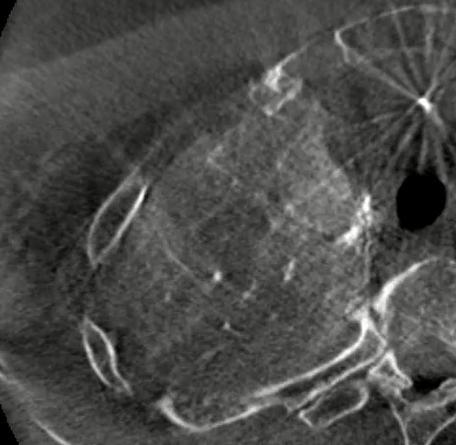

左上肺癌,锁骨上动脉造影,甲状颈干分支供应左上肺癌,反复使用单弯导管无法勾到责任血管,单弯导管热蒸汽成形后成功找到责任血管,微导管超选后CBCT证实肿瘤染色丰富后进行微球栓塞。